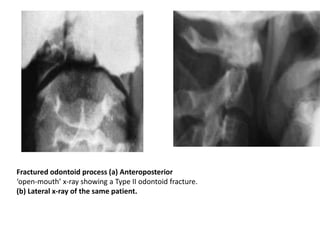

Fractured odontoid process (a) Anteroposterior

‘open-mouth’ x-ray showing a Type II odontoid fracture.

(b) Lateral x-ray of the same patient.

Fractured odontoid process(a) Anteroposterior ‘open-mouth’ x-ray showing a Type II odontoid fracture. (b) Lateral x-ray of the same patient.